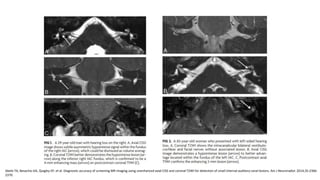

RM

Sensibilidad del 100%

• Gold estándar: T1 realce con contrate.

• Imágenes ponderadas en T2

• CISS o FIESTA

RM Sensibilidad del 100% •Gold estándar: T1 realce con contrate. • Imágenes ponderadas en T2 • CISS o FIESTA Abele TA, Besachio DA, Quigley EP, et al. Diagnostic accuracy of screening MR imaging using unenhanced axial CISS and coronal T2WI for detection of small internal auditory canal lesions. Am J Neuroradiol. 2014;35:2366-2370. Oh JH, Chung JH, Min HJ, Cho SH, Park CW, Lee SH. Clinical application of 3D-FIESTA image in patients with unilateral inner ear symptom. Korean J Audiol. 2013;17:111-117. American Academy of Otolaryngology–Head and Neck Surgery. Clinical Practice Guideline: Sudden Hearing Loss (Update). Otolaryngology– Head and Neck Surgery 2019, Vol. 161(1S) S1–S45 Cadoni G, Cianfoni A, Agostino S, et al. Magnetic resonance imaging findings in sudden sensorineural hearing loss. J Otolaryngol. 2006;35:310-316.

• FIESTA Sensibilidad: 84.6%-98% Especificidad:96-100% IC 95% interobservador Ordóñez L. VALIDACIÓN DE UNA PRUEBA DIAGNÓSTICA: SECUENCIA FIESTA DE IMÁGENES DE RESONANCIA MAGNÉTICA EN SCHWANOMA VESTIBULAR. Rev.Medica.Sanitas 15 (4): 18-25, 2012